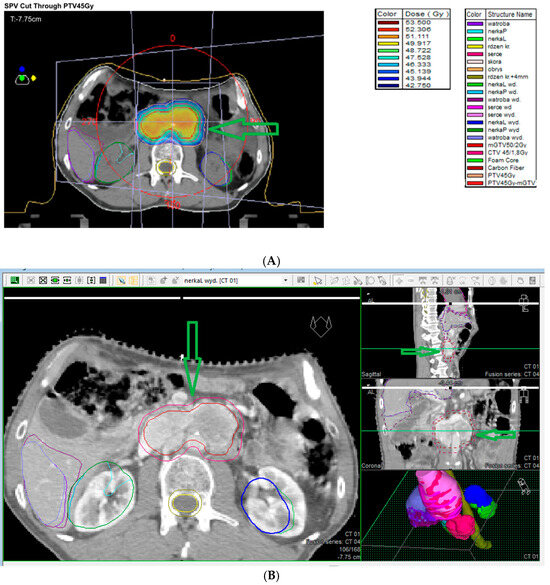

7.2. Abdominal EAPGLs and Pheochromocytomas

7.9. External Beam Radiotherapy (ERBT) and Hypofractionated Stereotactic Radiotherapy (hSRT)